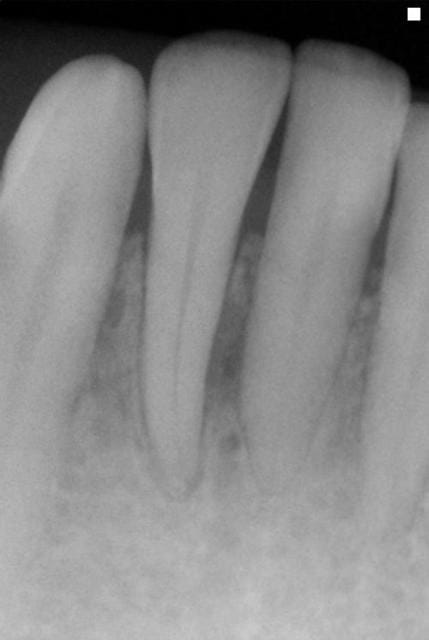

J'étais plus intervenu depuis longtemps parcequ'on m'avait dans les hautes sphères d'eugénol,demandé de me calmer,mais je peux pas laisser passer ça.On est dans un cas typique de guérison à la Sainte Carole, priez pour nous.La radio de départ elle est pourrie de chez pourrie.Comment on peut faire un diagnostic dans ces conditions?Comment on peut affirmer qu'il y a eu guérison, s'il n'y avait pas de lésion au départ.C'est absolument n'importe quoi.Il suffit de passer ces deux images à photoshop pour se rendre compte que les niveaux ne correspondent pas,et que sur la première image on est surexposé,ce qui brûle obligatoirement certaines zones de l'image,et que sur la deuxième on est sous exposé.Dans ces conditions,c'est ni six mois,ni trois,ni un jour,c'est en une seconde que je vous obtiens autant de guérisons miraculeuses que vous voulez.Y a vraiment personne qui réfléchit ici avec sa tête au lieu de s'extasier sur rien?pierres,va faire un stage de prise de radio avant de penser que tu es devenu un parodontiste émerite.

Meme si tu n y met pas les formes ta raison, sur la premiere radio on voit un defaut oseux evident masi on remarque aussi le sommet du septum interdentaire ... La preuve que la radio a été sur exposée

la différence d'exposition entre les deux clichés est évidente aussi, et c'est un défaut de la présentation.

CEPENDANT sur la couverture les deux radios ne sont pas prises avec la meme angulation!!! donc certainement pas comparables ( il n'y a qu'à regarder la projection de l'amalgame au collet de 36. certes il ya eu une amélioration mais je ne pense pas aussi impressionnante que ces images le laisse espérer.